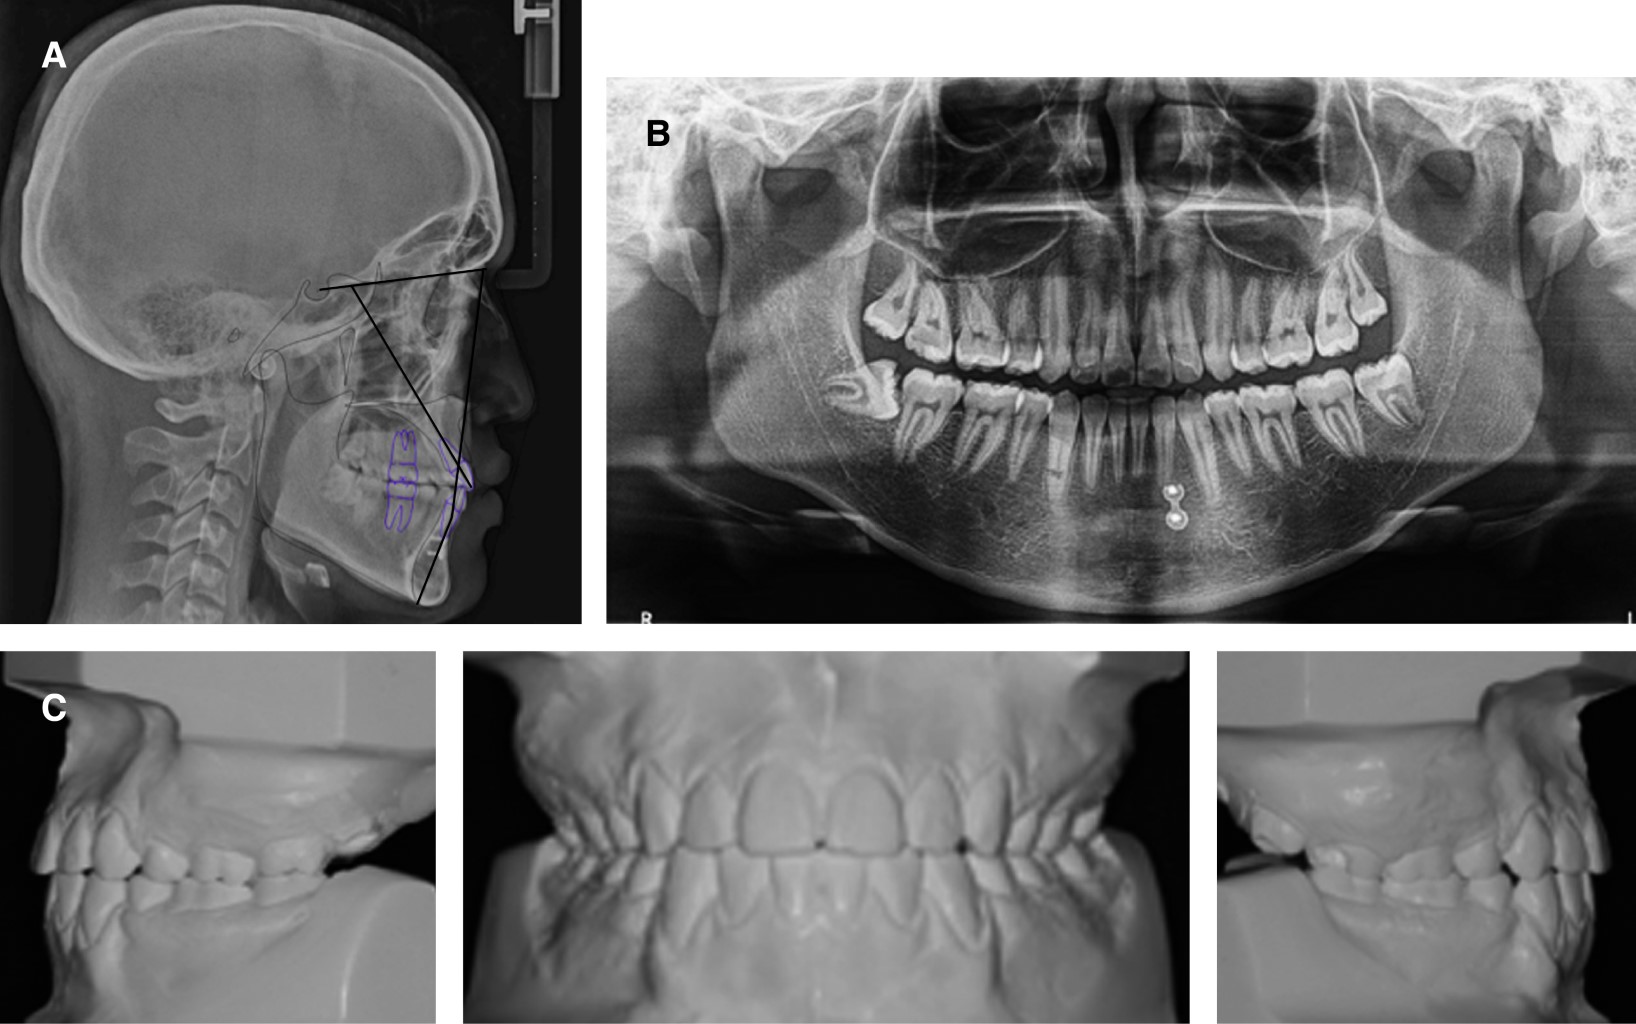

Análisis radiográfico

Radiografía lateral: en la cefalometría de Steiner fue trazada digitalmente en Dolphin versión 9.0 (Figura 3A), se encuentra una clase III esquelética por una hipoplasia maxilar, el ángulo mandibular se encuentra disminuido, indicando rotación hacia arriba y adelante. En los criterios dentales se encuentra una proinclinación y protrusión de los incisivos maxilares y mandibulares. En el análisis de tejidos blandos se presenta un surco mentolabial y un ángulo nasolabial disminuido y el labio inferior se encuentra ligeramente por delante de la línea E de Steiner (Tabla 1).

Radiografía panorámica: se encuentra una relación corona-raíz 1:2, un patrón de erupción dental normal, presencia de terceros molares inferiores y superiores en apicoformación, niveles de cresta ósea con altura adecuada, cóndilos simétricos, no presenta signos de enfermedad periodontal (Figura 3B).

Figura 3